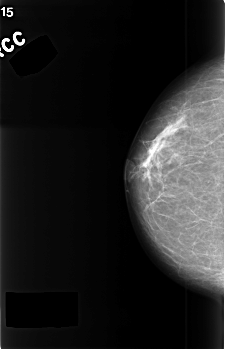

C_0388_1.RIGHT_CC

RIGHT_CC LINES 4528 PIXELS_PER_LINE 2920 BITS_PER_PIXEL 12 RESOLUTION 50 NON_OVERLAY

FILE: C_0388_1.LEFT_CC.OVERLAY

TOTAL_ABNORMALITIES 1

ABNORMALITY 1

LESION_TYPE MASS SHAPE LOBULATED MARGINS CIRCUMSCRIBED

ASSESSMENT 3

SUBTLETY 4

PATHOLOGY BENIGN

TOTAL_OUTLINES 1

BOUNDARY